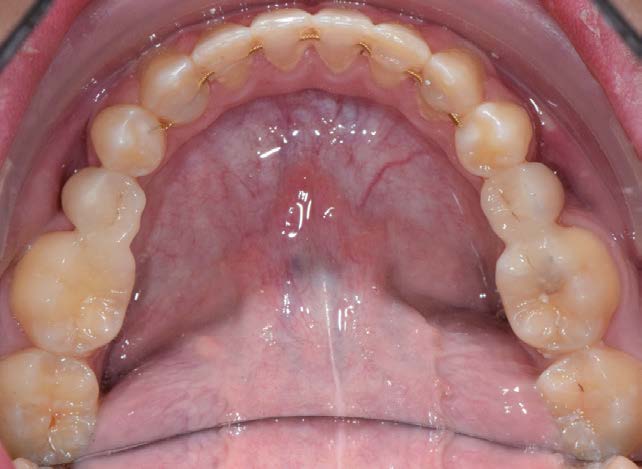

Figure 1

Le bon timing de coopération entre l’orthodontiste et l’omnipraticien est essentiel pour ce type de cas clinique [Fig. 1], où on constate la position extrême d’une molaire temporaire ankylosée jeune et non extraite à temps.

À ce stade, l’extraction a été jugée impossible par les experts.